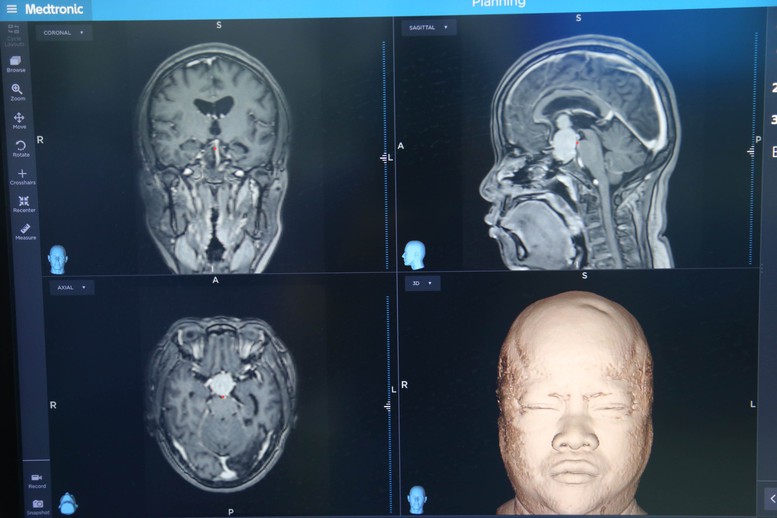

Hình ảnh khối u tuyến yên khổng lồ ở người bệnh - Ảnh: VGP/TM

Hiện nay, phương pháp kết hợp này là lựa chọn ưu tiên để can thiệp điều trị u tế bào tuyến yên khổng lồ (thường có kích thước 1 chiều từ 4cm trở lên, hoặc thể tích 10 cm3 trở lên), điều trị u xâm lấn xung quanh và các trường hợp tái phát nhiều lần.